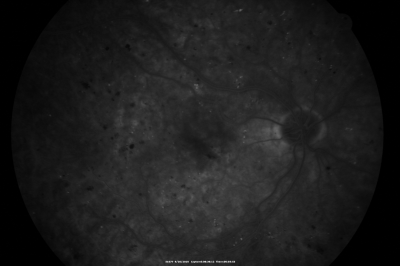

BDR OD with Edema

57-year-old man has diabetic retinopathy in both eyes.

Diabetic for 14 years with HgB A1C often over 10.

VISUAL ACUITY: OD 20/30, OS 20/40. PDR OS BDR OD

NVD - Neovascularization of the Disc - Macular Edema